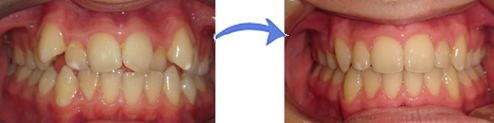

Resim 1: Kliniğimizde tedavisi yapılmış ve diş çekimine gerek duyulmamış bir hastanın ilk ve tedavi sonrası hali.